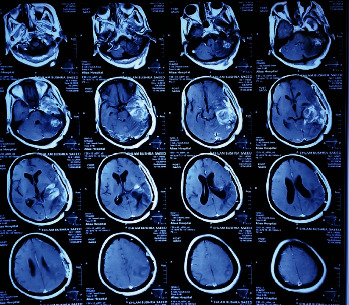

Introduction: Radiation-induced gliomas (RIGs) were reported in the literature in general. In most of the reported cases and the reviewed articles, patients have a history of primary intracranial tumors like craniopharyngioma, medulloblastoma, and ependymoma, and the commonly resulting secondary tumors are meningiomas and sarcomas, mainly not gliomas. Case Presentation. A 50-year-old woman had a history of left scalp temporal region periauricular squamous cell carcinoma, which was verified by the histology result of a biopsy 11 years ago. On the basis of that, she began receiving low-dose radiation sessions when she was 39 years old. She exhibits cranial symptoms and a radiological sign of cancer 9 years later. After a successful excision procedure, histology revealed diffuse astrocytoma Grade 2. Our case is suspected to fit the criteria for being identified as RIG, which is a syndrome that is thought to occur infrequently in the literature.

Conclusion: In conclusion, the way that this condition manifested in our case is considered rare due to old age and the low doses of radiation received. Despite being an important part to confirm the diagnosis, genetic studies were unfortunately not done in our case, but we mainly based on the criteria mentioned by Cahan et al., which are mainly taken from the clinical history and histopathology. Here, we present an example of considering such a diagnosis when suspected clinically, but a genetic study for confirmation should be thought of even if it is not available in the locality.